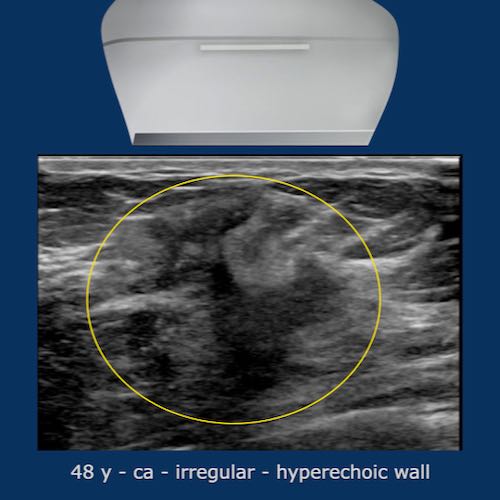

Quầng tăng âm (Hyperechoic halo)

Một dấu hiệu thường gặp trong ung thư vú là quầng tăng âm bao quanh khối giảm âm.

Quầng này là một phần của khối u và cần được tính vào kích thước đo của khối u.